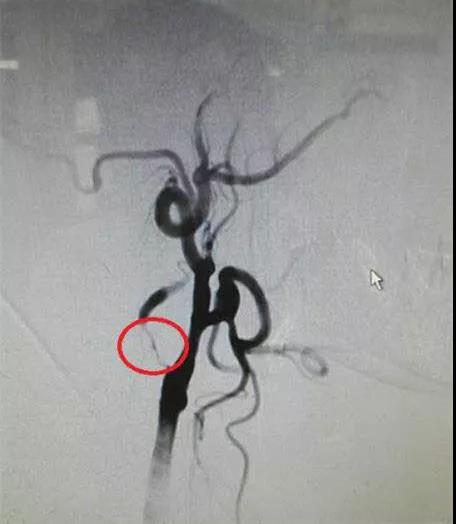

患者术前脑血管造影图,显示右侧颈内动脉重度狭窄>98%,接近闭塞

大脑是身体的“总司令部”,而颈动脉则是负责大脑供血的主要血管,当颈动脉出现堵塞,就可能出现脑缺血的情况,表现为头昏乏力、记忆力减退,甚至认知能力下降、肢体麻木等,严重的会出现偏瘫、失语,甚至危及生命。 近日,我院神经外科成功开展郴州市首例颈内动脉内膜剥离术,患者现已康复出院。 患者60岁,男性,以反复TIA(短暂性脑缺血发作)发作,多发脑梗入我院神经内科,行 DSA造影显示右侧颈内动脉重度狭窄>98%,接近闭塞,患者反复咨询后不愿接受颈动脉支架植入术,经神经外科彭璞主任会诊后转入神经外科。彭璞主任带领全科医务人员对病案讨论,充分分析病情:患者频发TIA发作,脑梗塞,有随时可能再次发生大面积脑梗塞风险。药物治疗无法改善脑缺血,病变侧颈内动脉几乎完全闭塞,支架可能无法通过。且患者因经济原因,拒绝接受支架植入术,只有外科手术行颈动脉血管重建,才能改善脑血供。综合以上因素,考虑行颈内动脉内膜剥离术。